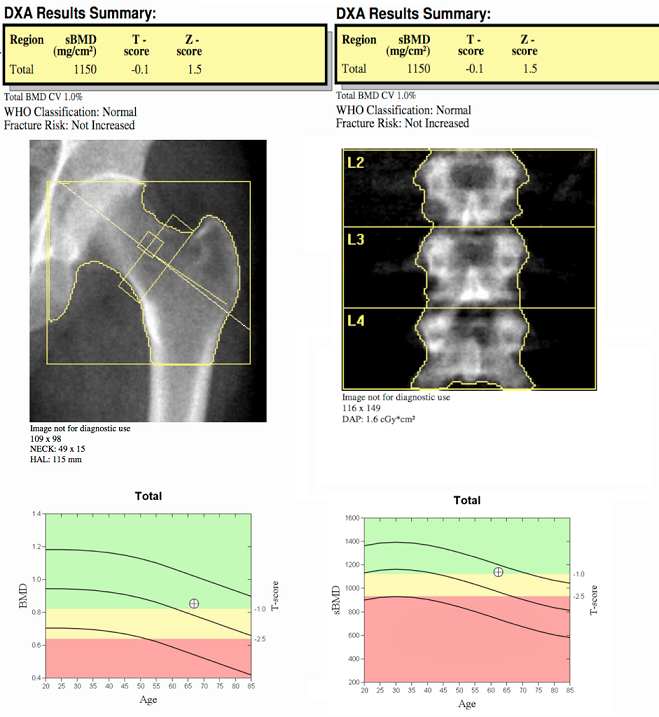

Full-body DEXA exams are offered at our hospital imaging centers. Bone densitometry, using DEXA (dual-energy X-ray absorptiometry), safely, accurately and painlessly measures bone density and the mineral content of bone. DEXA is the most widespread, non-invasive test for the detection of osteoporosis, and is the best way to identify individuals who are at increased risk for future fractures. Based on your test results, your physician can suggest treatment options from exercise and lifestyle changes, nutritional supplements or medication. The goal of diagnosis and treatment is to prevent fractures.